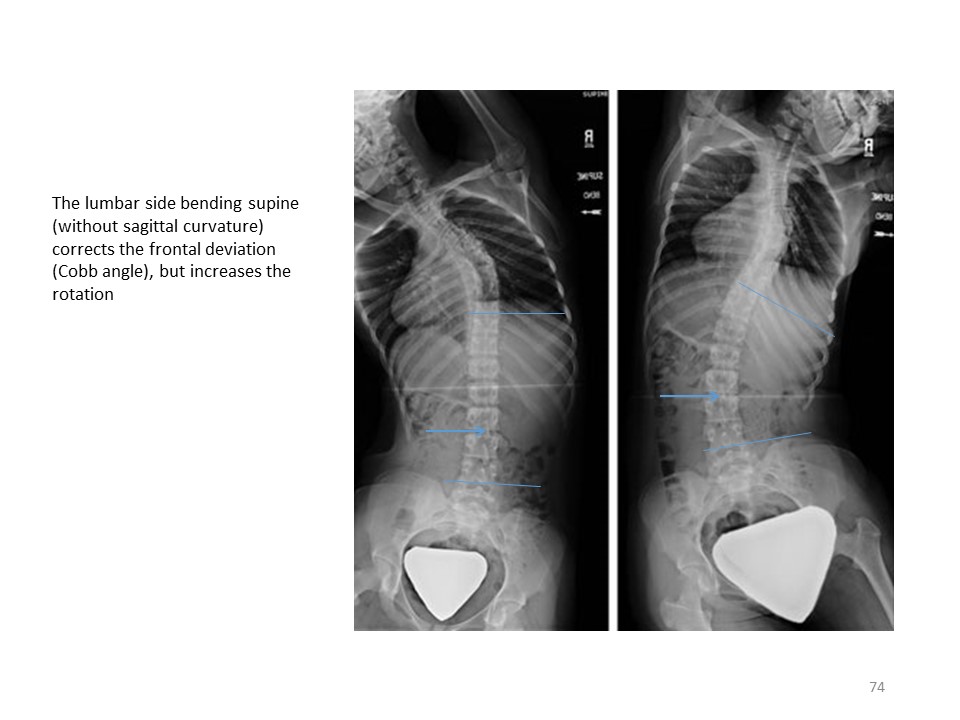

The laws of coupled movements at the level of the spine have also been described in the context of vertebral manipulations. For the same frontal inflection, the direction of rotation can vary depending on the sagittal plane. To obtain a derotation with scoliosis, the sagittal plane must be positioned in isostatic balance. In case of a flat back, the scoliotic rotation can be accentuated. |

|

The illustration of this principle is obtained experimentally by creating a structural scoliosis with a single bending in the frontal plane. |

In some corrective bendings performed in the supine position, the lumbar rotation can be accentuated. |

It is the same here at the thoracic level. |